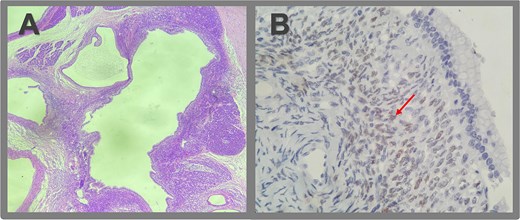

Gross pathology revealed a cystic lesion lined by mucinous epithelium with regular nuclei and no atypia. The capsule consisted of dense connective tissue with cellular stroma consistent with ovarian-type stroma (Figs 2 and 3). The final diagnosis was an MCN with low-grade dysplasia, measuring 3.7 cm at its largest diameter. Capsular rupture with granulation tissue and prior hemorrhage extending to the posterior pancreatic surface was documented. Resection margins were free of disease, no invasive carcinoma was found, and all lymph nodes were negative. Immunohistochemical staining demonstrated estrogen receptor positivity.

Microscopic pathologic examination. (A) Histological sections of the cystic lesion reveal a mucinous epithelial lining with regular nuclei, without atypia or architectural complexity. The capsule consists of dense connective tissue and contains areas of more cellular stroma, characterized by spindle cells without significant atypical or mitotic activity (ovarian-like stroma). A region of the capsule is replaced by granulation tissue, with evidence of prior hemorrhage and fibrosis extending to the posterior surface of the pancreas. No evidence of invasive neoplasia is observed. (B) Immunohistochemistry revealed strong positivity for estrogen receptors in the ovarian-type stromal cells, indicated by brown staining (arrow).